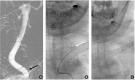

Unfavorable Vascular Anatomy during Endovascular Treatment of Stroke: Challenges and Bailout Strategies

The benefit of mechanical thrombectomy (MT) in acute ischemic stroke (AIS) due to large vessel intracranial occlusions is directly related to the technical success of the procedures in achieving fast and complete reperfusion. While a precise definition of refractoriness is lacking in the literature, it may be considered when there is reperfusion failure, long procedural times, or high number of passes with the MT devices. Detailed knowledge about the causes for refractory MT in AIS is limited; however, it is most likely a multifaceted problem including factors related to the vascular anatomy and the underlying nature of the occlusive lesion amongst other factors. We aim to review the impact of several key unfavorable anatomical factors that may be encountered during endovascular AIS treatment and discuss potential bail-out strategies to these challenging situations.